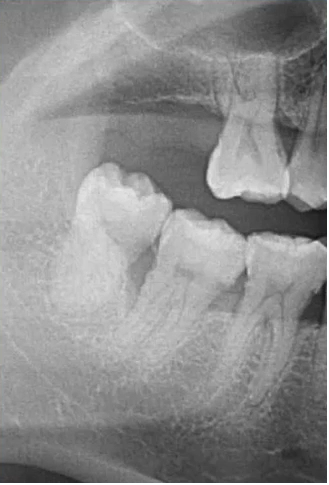

【病例1】

9岁,男孩,因右上面颊部肿胀来源就诊

55深龋→根尖炎→面颊肿胀

根尖片视野范围较小,曲断检查结果:乳5颌骨根方有含牙囊肿的存在。

曲面断层片怎么看口腔精读 | 一次性教你看懂曲面断层片!_https://www.jmylbn.com_新闻资讯_第28张